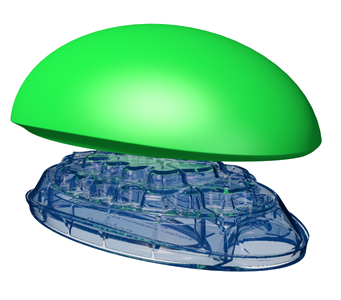

The Backpod for upper back and neck pain - premium home treatment for the iHunch and other conditions.

So, the Backpod and its simple home program are specifically designed to pull you back towards pain free perfect posture - see our PERFECT POSTURE page for why posture is important. The Backpod itself is an international award-winning Classification 1 medical device. Lying back on it uses your upper body weight to stretch out a tightened, stooped middle and upper back, and tight rib cage. See THE BACKPOD page for more detail.